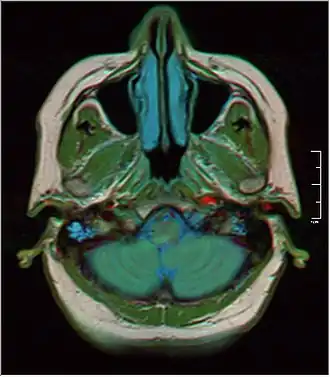

![]() MRI showing fluid in mastoid air cells | |